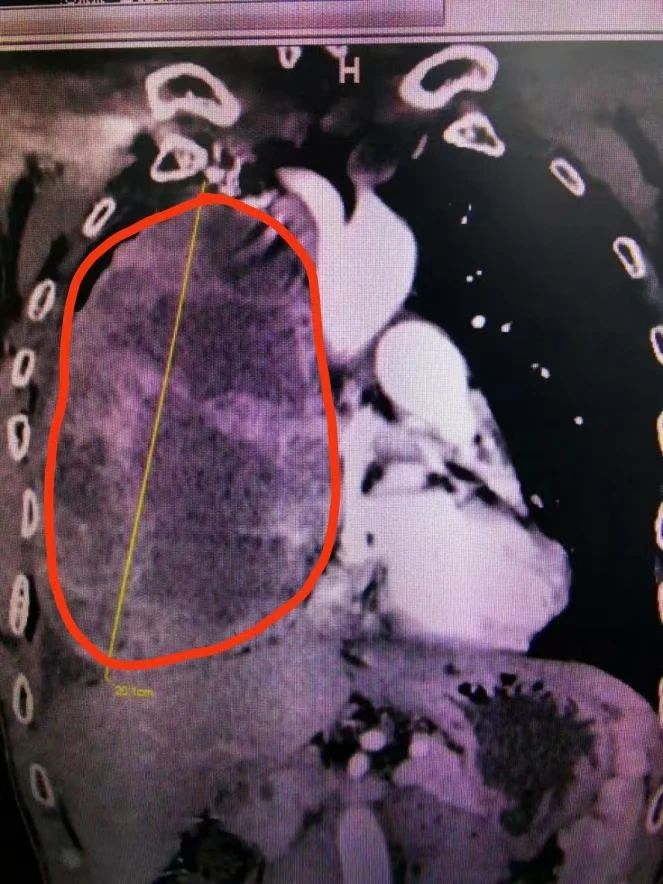

CT检查(红圈内为肿瘤)

实际上,李先生的情况确实比较棘手。邓意平主治医师表示,患者的胸部增强CT显示前纵隔巨大肿瘤,因肿瘤巨大,肿瘤内滋养血管非常丰富,并累及右侧胸腔大部,右肺受压明显;与心包、无名静脉、上腔静脉、右肺动脉等重要血管界限不清。

邓意平主治医师介绍,纵隔是一个解剖区域,位于两肺之间,胸骨和胸椎为前后界。纵隔内原发肿瘤以良性多见,也有部分恶性。因其内有重要器官,原则上纵隔肿瘤一经发现,建议手术治疗,对于直径大于10厘米的肿瘤被称之为巨大纵隔肿瘤,该患者的肿瘤达20多厘米的情况实属罕见。